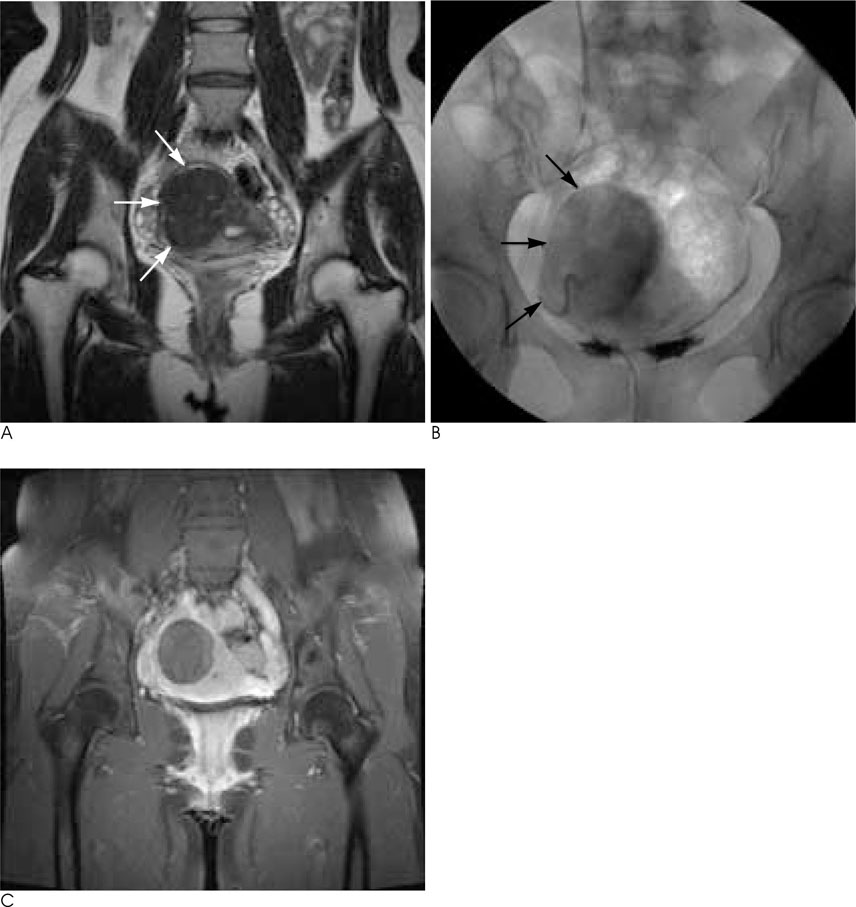

Practical Application of a Coronal MR Image during a Uterine Fibroid Embolization (UFE)

To assess the role of coronal MR images during uterine fibroid embolization (UFE).

A prospective study of 100 consecutive patients who underwent a uterine fibroid embolization was performed. The average age at embolization was 40.2 years (range, 19-49 years). The size of the predominant fibroids ranged from 2.5 cm to 21.0 cm (mean, 7.5 cm). The embolic agents included non-spherical polyvinyl alcohol particles. The angiographic and spot images after embolization were compared with coronal MR images. The patterns were divided into three categories: Matching, Undetermined, and Mismatching.

Coronal MR images were correlated with angiographic or single shot images of the uterus after embolization in 94 cases, undeterminined in three cases, and mismatched in three cases. Post-embolization aortographies were not helpful in patients showing complete matching images. In three cases of mismatching, two had ovarian collateral supplies to predominant fibroids in the uterine fundus and the remaining patient had an internal pudendal artery of collaterals to fibroid. Mismatching spot images combined with MRI allowed us to find other collateral vascularities.

Coronal MR images provided comprehensive information for the appropriate UFE. When perfectly matched, we could make sure that a particular UFE is appropriate without concern for collaterals.